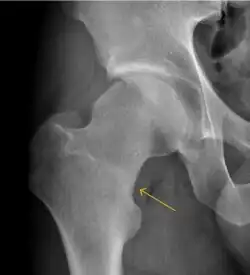

MRI has been shown to have 100% sensitivity and specificity in prospective studies of occult hip fractures. These fractures were diagnosed by bone marrow edema and a low signal fracture line, mainly on T1 or T2 weighted images (Figure 10).[1]

Figure 10:

-

Stress femoral neck fracture in a young athlete barely visible in X-ray film as a sclerotic line (arrow)[1] -

In this case, Tc 99 scintigraphy shows a band of uptake[1] -

Furthermore, T1 (left) and DP fat saturated (right) weighted MR images showed the fracture line and a pattern of edema.[1]

Radiological signs of transient osteoporosis of the hip include localized osteoporosis of the femoral head and neck (Figure 8). Nevertheless, final diagnosis has to be made with MRI to differentiate it from avascular necrosis and from insufficiency or stress fractures of the femoral head or neck. In case of AVN, radiographs can only demonstrate delayed or advanced signs. Staging according to Ficat classification ranges between normal appearance (stage I), slight increased density in the femoral head (stage II), subchondral collapse of the femoral head with or without “crescent” sign (stage III), and advanced collapse with secondary osteoarthritis (stage IV). In the case of stress or insufficiency fractures X-ray sensitivity has been proven to be much lower than MRI, which is currently the gold standard.[1]